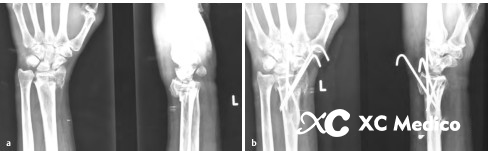

9. Радиальный стилоидный перелом с дорсальным смещением. После сокращения исправьте два радиальных стилоидных провода Kirschner: один на дорсальной стороне, а другой на ладони, к кончику стилоида. (Рисунки A и B ниже)